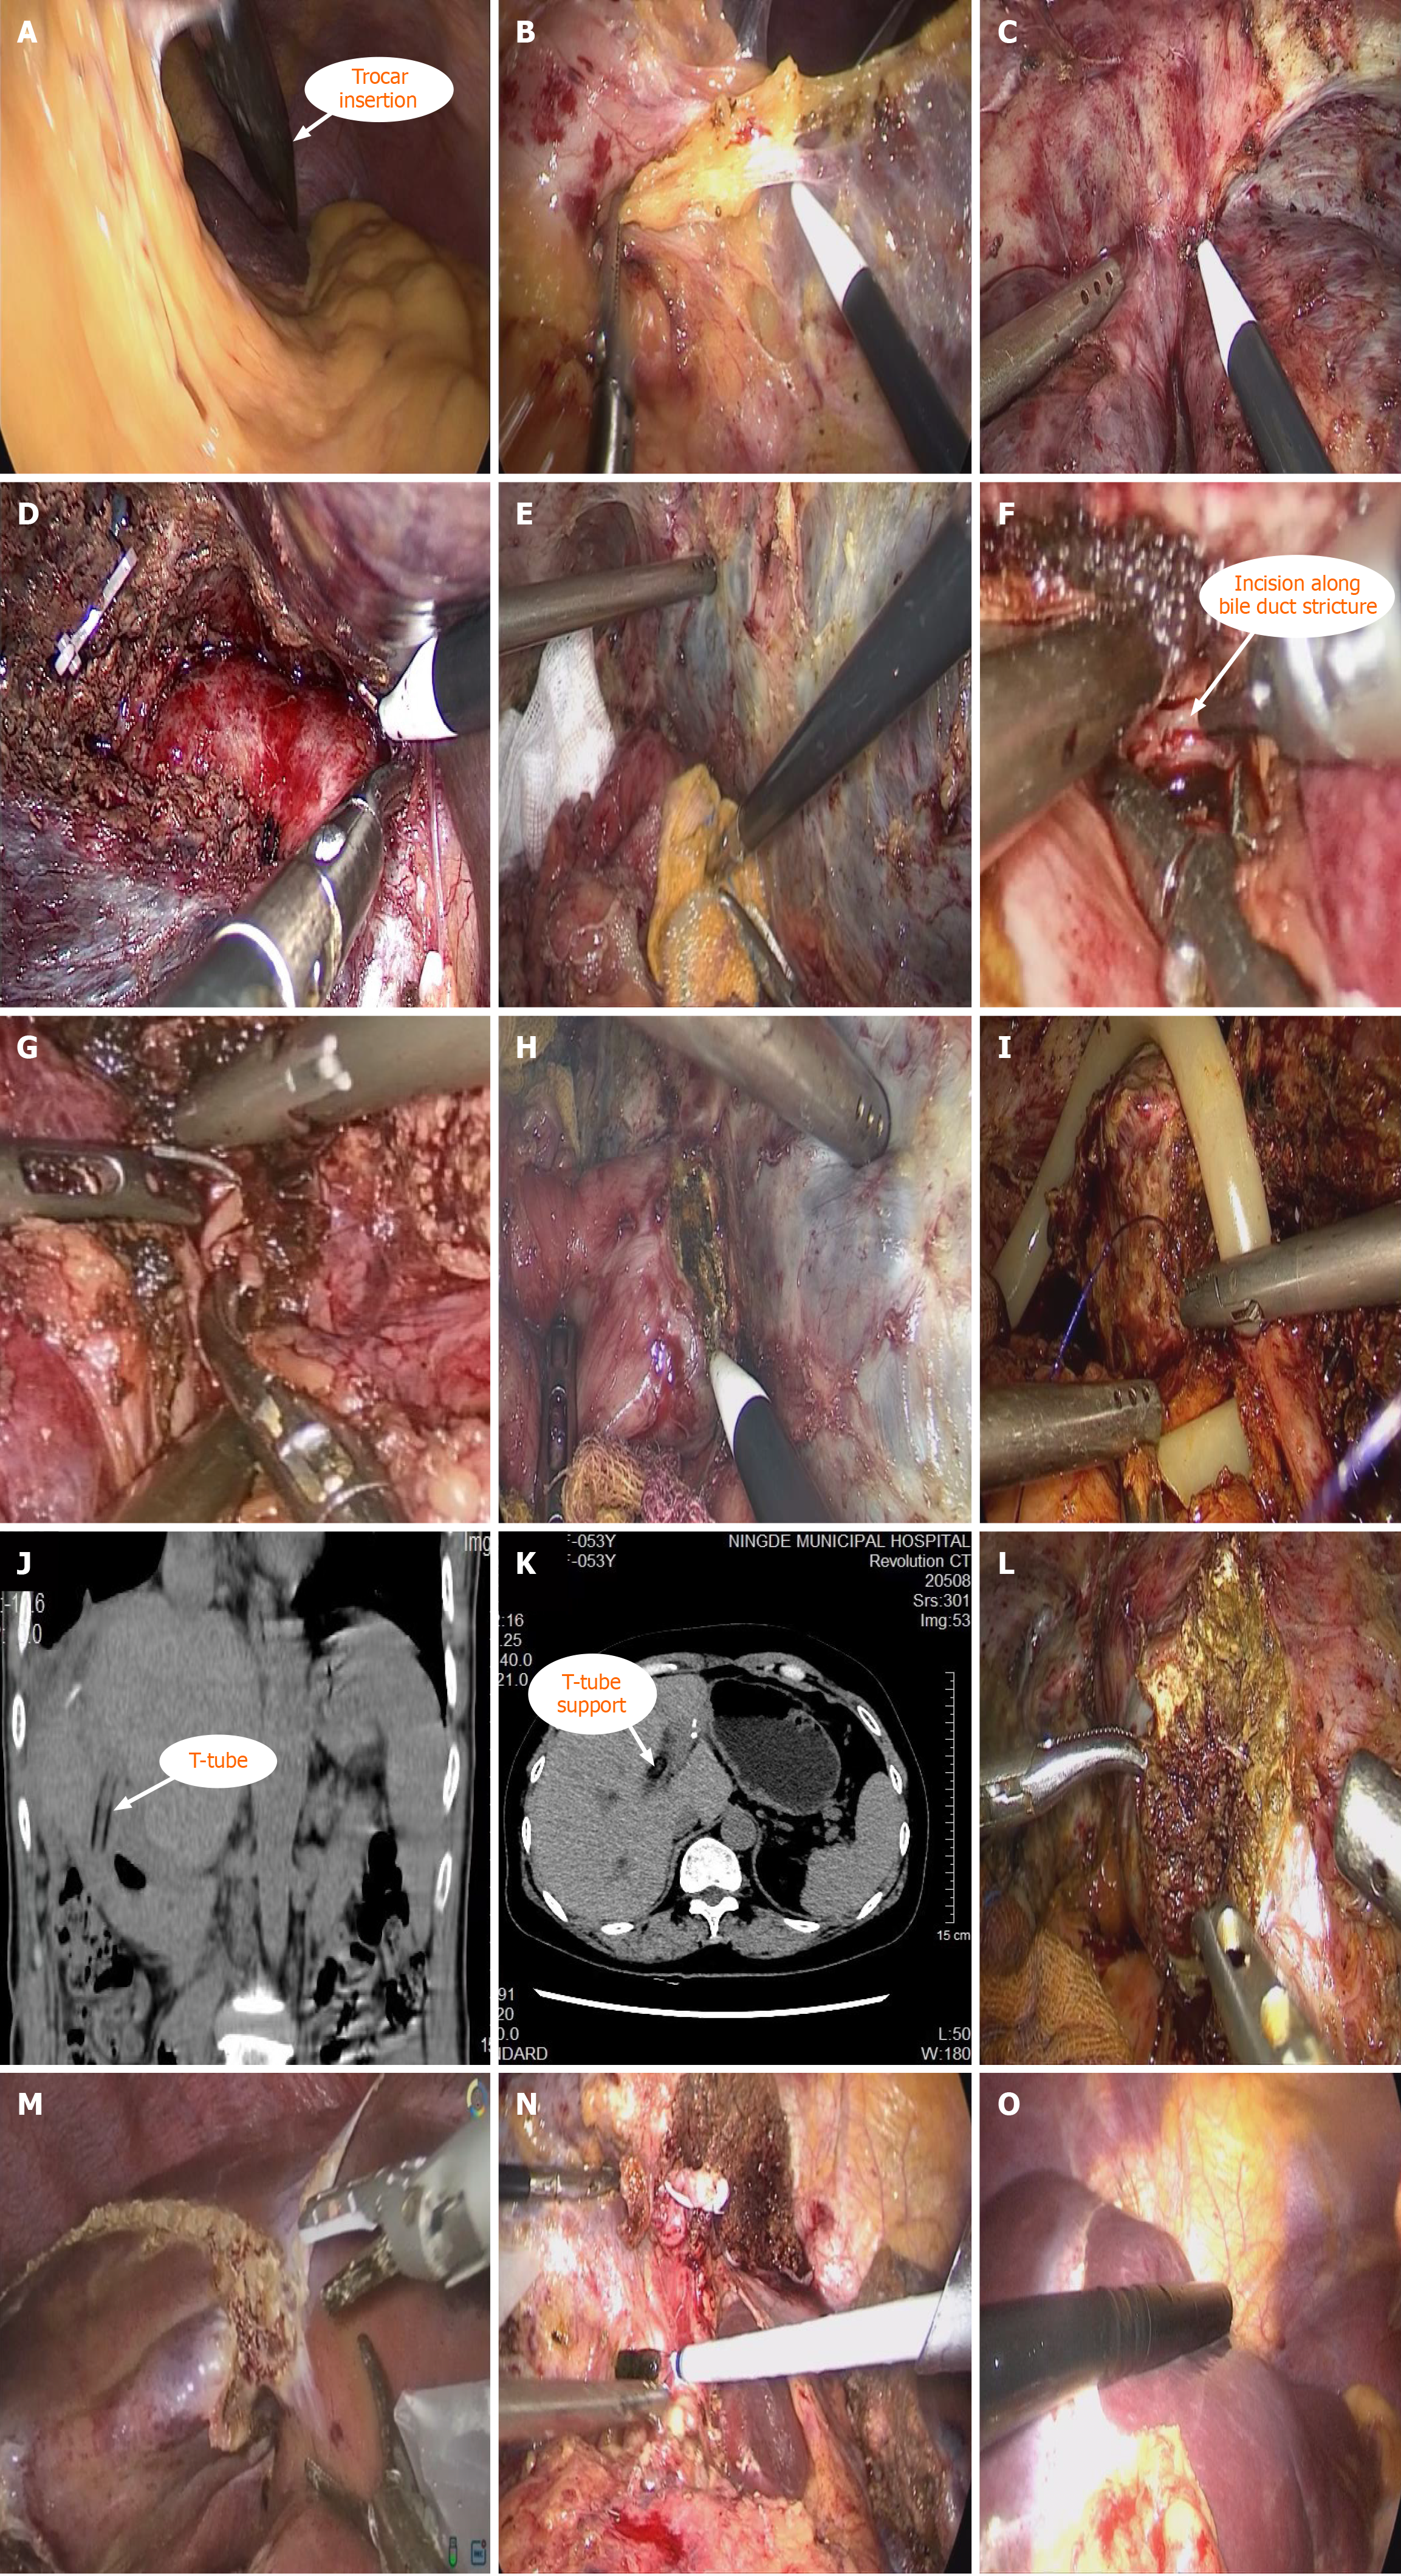

Figure 2 Intraoperative and postoperative images of selected cases with hepatolithiasis.

A: Endoscopic view of the laparoscopic trocar insertion site; B: Adhesiolysis along the liver capsule to expose the hepatic hilum; C: Dense adhesion between the liver surface and diaphragm, requiring meticulous dissection; D: Dissection of a dilated bile duct using Laennec’s capsule as an anatomical landmark; E: Placement of iodine-soaked gauze around the anastomosis to prevent intra-abdominal contamination; F: Longitudinal incision of the biliary stricture along its axis; G: Suturing of the incised stricture to restore biliary patency and ensure adequate drainage; H: Exposure of a stenotic bile duct following adhesiolysis; I: Intraoperative placement of a T-tube through the revised biliary-enteric anastomosis; J: Postoperative computed tomography confirming T-tube positioning and biliary decompression; K: Postoperative computed tomography confirming complete stone clearance and hepatic parenchymal integrity; L: Partial resection of liver segments 4b and 5 to access the dilated bile duct; M: Resection of liver segments 4b and 5 to expose the stenotic bile duct; N: Choledochoscopic basket extraction of impacted stones under direct visualization; O: Intraoperative ultrasound localization of stones and adjacent hepatic veins.